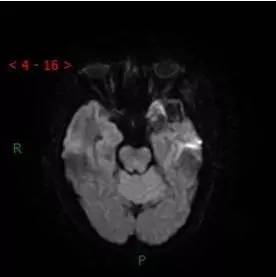

DWI

解析:本病例为中颅窝至颞下窝沟通性病变,对周围骨质主要呈膨胀压迫性改变,伴囊变、出血。

病理:(中颅底内外沟通肿瘤) 神经鞘瘤,伴出血,局灶细胞较丰富。免疫组化结果显示:EMA(-), P53(-), S100(3 ), NF(-), PR(-), desmin(-), Ki-67( ,5-10%)